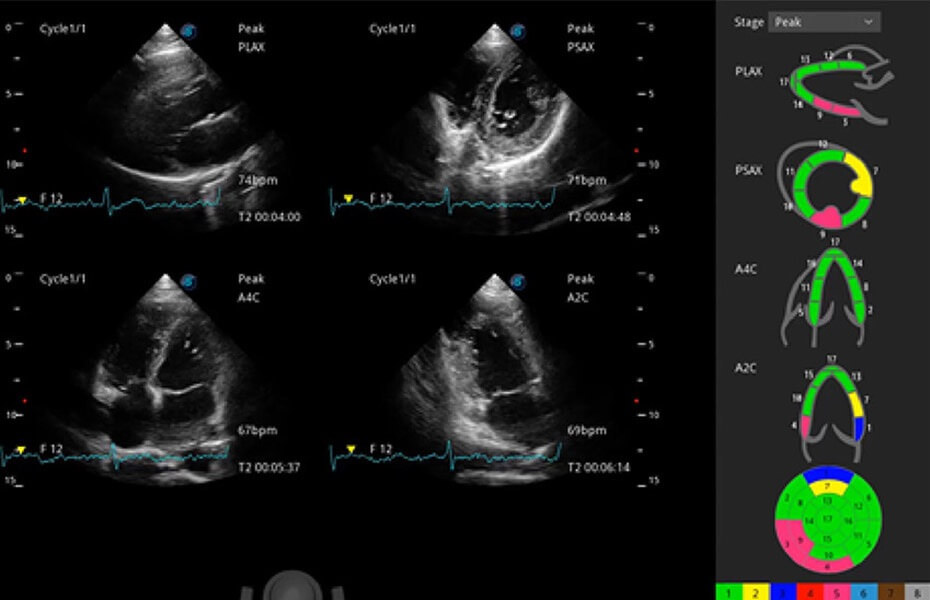

ProPet 60 作為一款高端臺(tái)式動(dòng)物超聲設(shè)備,為動(dòng)物醫(yī)生的日常診斷提供了一系列貼合動(dòng)物臨床需求、解決臨床實(shí)際問題的高級(jí)成像功能。憑借全系列高清探頭,滿足醫(yī)生對(duì)腹部、心臟、生殖、淺表、肌骨等成像的所有需求,切實(shí)幫助您提升檢查效率,提高診斷信心。